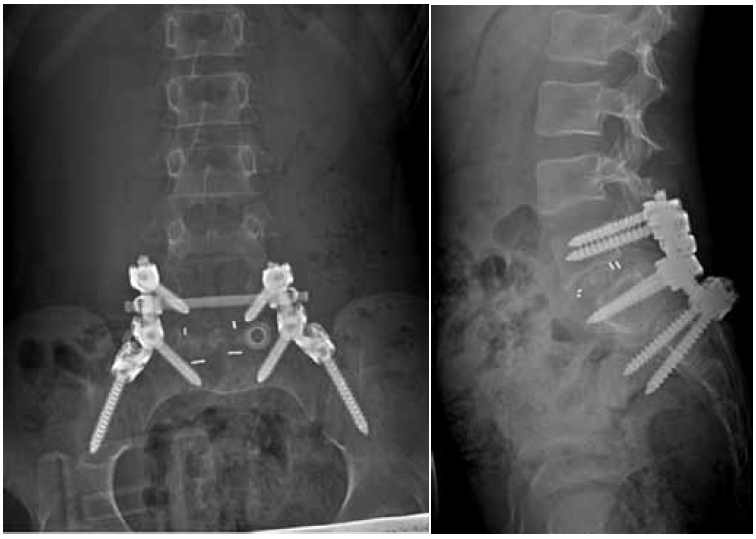

Considering the persistent pain syndrome after the conservative treatment and progressive nature of spondylolisthesis of L5, the following surgical intervention was performed: L5 laminectomy, microsurgical decompression of the spinal cord roots, complete reduction of the L5 vertebra, transpedicular fixation of the L5–S1 with additional fixation in the pelvic bone, and posterior interbody fusion of L5–S1. The duration of the surgery was 355 mins; the volume of blood lost was 800 ml. The patient was activated on the day 2 after surgery. During the postoperative period, the radicular pain syndrome had regressed completely, and no neurological disorders were detected. According to the control radiography, the restoration of the anatomical relationship of the vertebrae was noted. The position of the screws and implants was correct (Fig. 2). During the follow-up period, the patient had no complaints. After 1.5 years, MSCT revealed the formation of a reliable artifactual block, and the integrity of the surgical hardware was preserved (Fig. 3).

Fig. 2. Radiography of the lumbar spine in two views immediately after the surgery